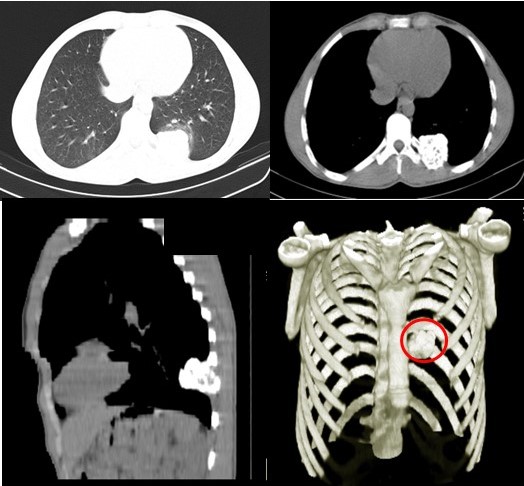

Paciente masculino de 22 años de edad, sin antecedentes patológicos personales ni familiares, quien es referido debido a que un examen radiográfico posteroanterior y lateral, se evidencia como hallazgo incidental imagen radiopaca de apariencia redondeada, de unos 5 cm de diámetro, localizada en el décimo (10o) arco costal posterior izquierdo (Figura7), y por lo cual fue remitido a la consulta externa de la Unidad de Cirugía de Tórax de nuestro centro hospitalario en donde es valorado.

El examen físico practicado se encontró dentro de límites normales, motivo por el cual se ordenan exámenes complementarios de laboratorio e imágenes de TC de tórax con ventana y reconstrucción de pared torácica ósea, asimismo, survey óseo. Exámenes complementarios de laboratorio dentro de parámetro normales.

En la TC de tórax con reconstrucción en 3D, se evidenció imagen hiperdensa con áreas hipodensas en su interior, redondeada de bordes bien definidos microlobulados que mide 4,3 cm x 4,3 cm a nivel del 1/3 proximal del décimo (10o) arco costal posterior izquierdo con protrusión de dicha lesión hacia parénquima pulmonar y partes blandas dorsal compatible con lesión neoplásica benigna. Resto del plano óseo y blando sin evidencia de lesiones (Figura 8).